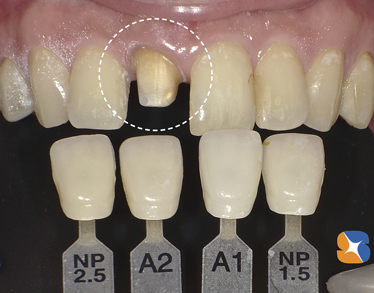

まず、セレックに読み込みカメラを用いて、削った直後の状態を入力します。

まず、セレックに読み込みカメラを用いて、削った直後の状態を入力します。

セレックの設計画面で、理想的な形をDr.が設計します。

セレックの設計画面で、理想的な形をDr.が設計します。